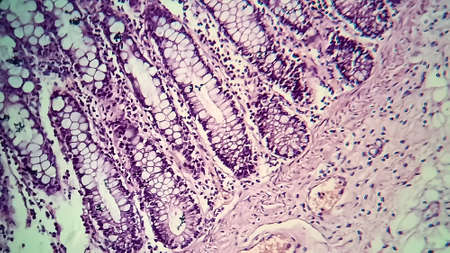

Cross section of intestinal glands (crypts of Lieberkühn) showing mucous goblet cells. Human colon.